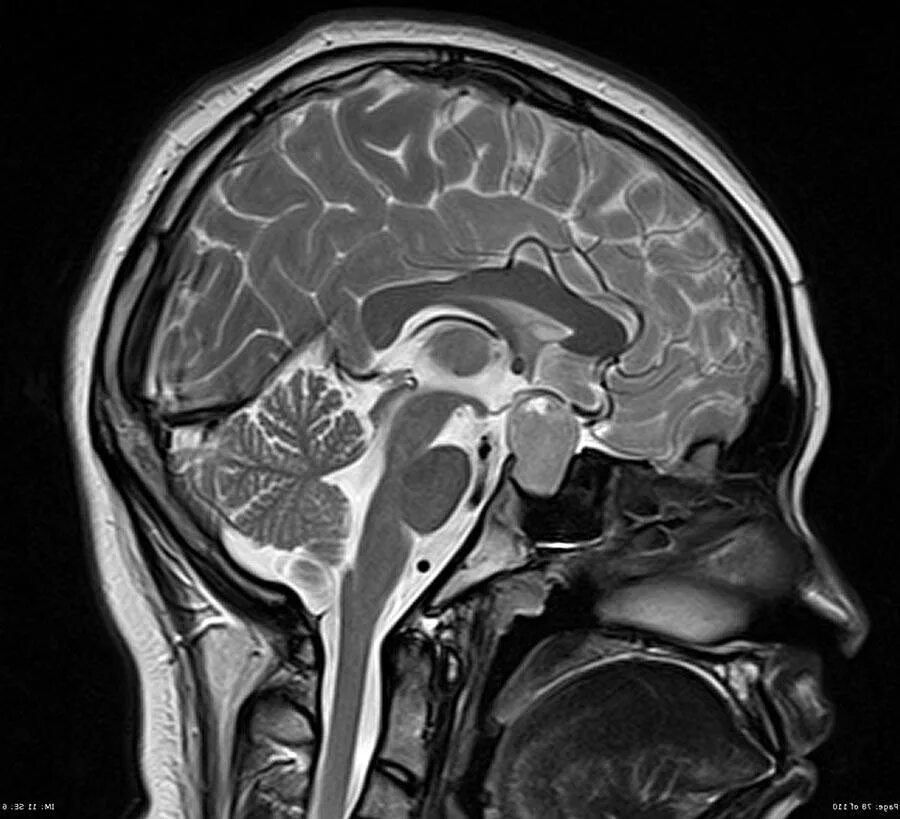

Что покажет мрт головного мозга с контрастом